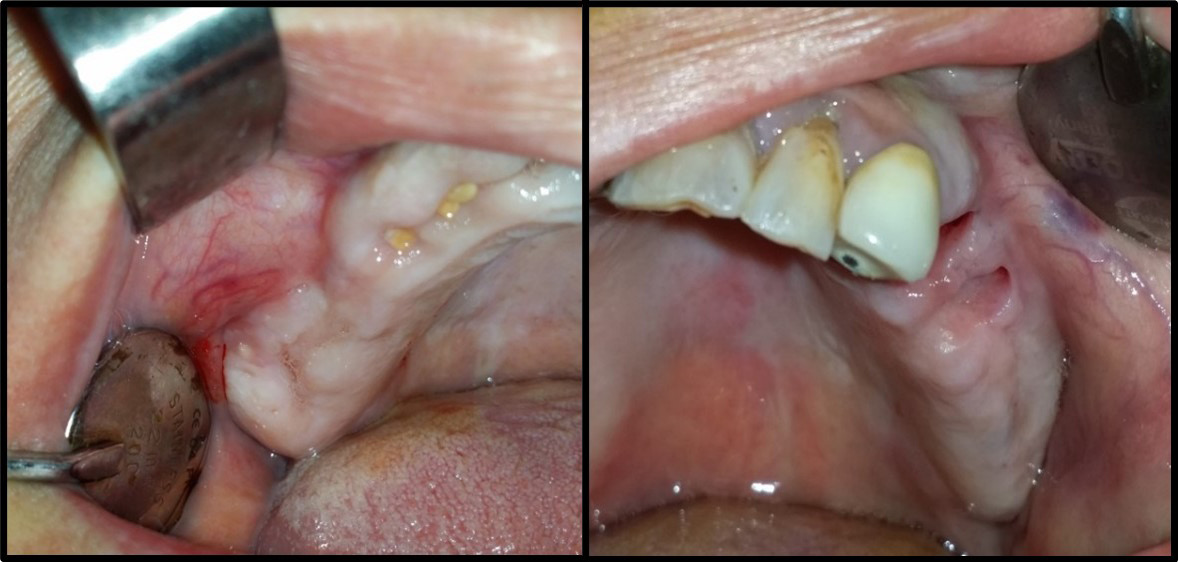

The mouth was disinfected with 0.12% chlorhexidine rinses, the skin around the mouth was disinfected with a polyvidone iodine solution and the surgical area was isolated using sterile surgical scrubs. Local (buccal and palatal) anesthesia utilized 2% lidocaine hydrochloride (HCl) and epinephrine (1:80,000) (Figure 2). A trapezoid-shaped, full-thickness mucoperiosteal buccal flap was then created (Figure 3).

Using a piezosurgical device with appropriate saline irrigation, a bony window with rounded corners was created to reduce perforation during lifting. It had dimensions of 12–15 mm in length and 10 mm in height based on the size of the area to be grafted. A CBCT radiograph indicates the thickness of the bony window, which facilitates its preparation; 2–3 mm above the bottom of the maxillary sinus to enable sufficient vision during work and reduce the tension of the sinus membrane in the initial lifting phase. However, the window should not be enlarged much, as the surrounding walls aid bone healing (Figure 4).

The sinus membrane was elevated with a sinus lift tool – the Dentium Advanced Sinus Kit (DASK) (Dentium, Cypress, USA), and for the grafting of the maxillary sinus, the mixture of CS or TCP with A-PRF was used (Figure 5). When using the TCP/A-PRF compound, we placed a collagen membrane on the bony window (Figure 6). The CS/A-PRF compound does not require any membrane, as a catalyst is added to the CS graft to harden fast. As such, the CS graft replaces the membrane due to its hardening and slow absorption properties.15

Interrupted suturing employed 4-0 Prolene sutures and a reverse cutting needle (Ethicon US, Cincinnati, USA) (Figure 7). The patients received post-surgery instructions and a medical prescription, and had a follow-up appointment to remove the sutures (Figure 8).